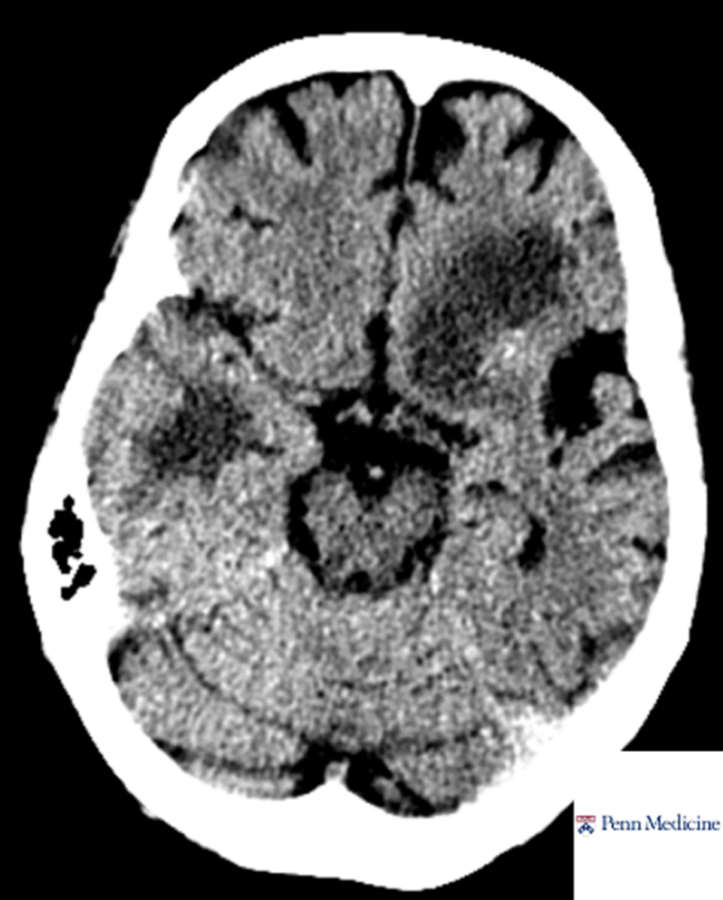

60-year-old woman with weight loss, fevers, confusion

A 60-year-old woman with history of treated pulmonary adenocarcinoma and renal and pancreas transplantation on chronic immunosuppression presents with progressive weight loss, fevers, and confusion.

Published Date: February 26, 2026